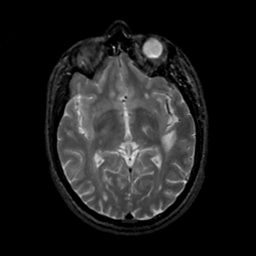

MR Study #18, July 21, 1991 -- Slice #24